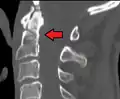

Fractures of the dens are classified into three categories according to the Anderson Alonso system:

- Type I fracture - Extends through the tip of the dens. This type is usually stable.

- Type II fracture - Extends through the base of the dens. It is the most commonly encountered fracture for this region of the axis. This type is unstable and has a high rate of non-union.

- Type III fracture - Extends through the vertebral body of the axis. This type can be stable or unstable and may require surgery.[1]

Type 3 odontoid fracture -